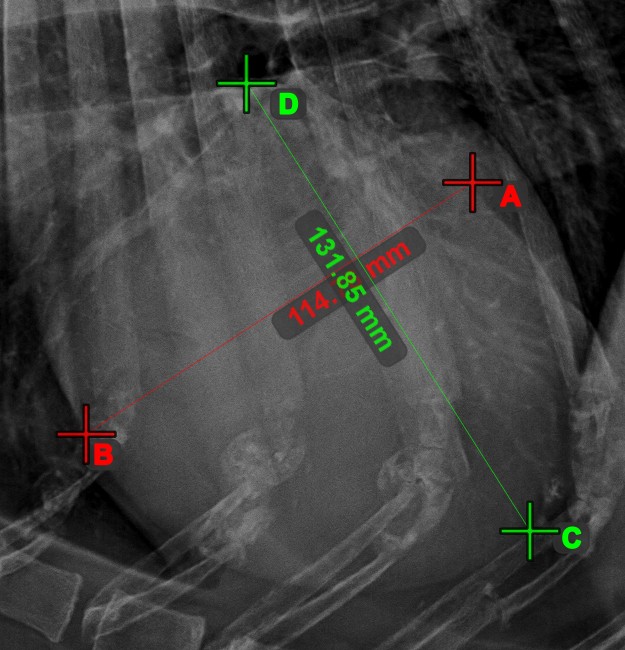

Vonalak metszéspontja¶

Gyorsan és pontosan találja meg és jelölje két meglévő vonal közti metszéspontot a Vonalak metszéspontja eszközzel.

Válassza ki az eszközt a bal oldali eszköztárból, és rendelje hozzá az egyik elérhető egérgombhoz. Válasszon ki két, a jelenetben már meglévő vonalat a mérés elvégzéséhez. A vonalak metszéspontja automatikusan kiszámításra kerül és jelölésre kerül a jelenetben. Két vonal metszéspontját mindig az X betű jelzi.

Információ

Ha két vonal közvetlenül nem metszi egymást, a jeleneten azok meghosszabbított vetületeinek metszéspontja lesz jelölve.